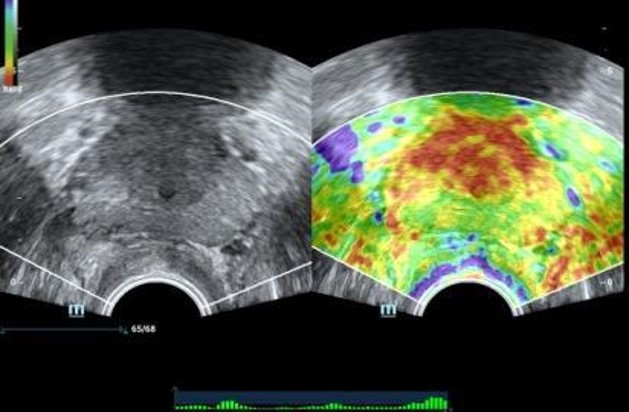

Elastografia prostaty

Natural Touch Elastografia, Strain Elastografia

Sound Touch Elastografia

Vyhodnotenie tuhosti prostaty pre lepšiu diagnostiku rakoviny prostaty.